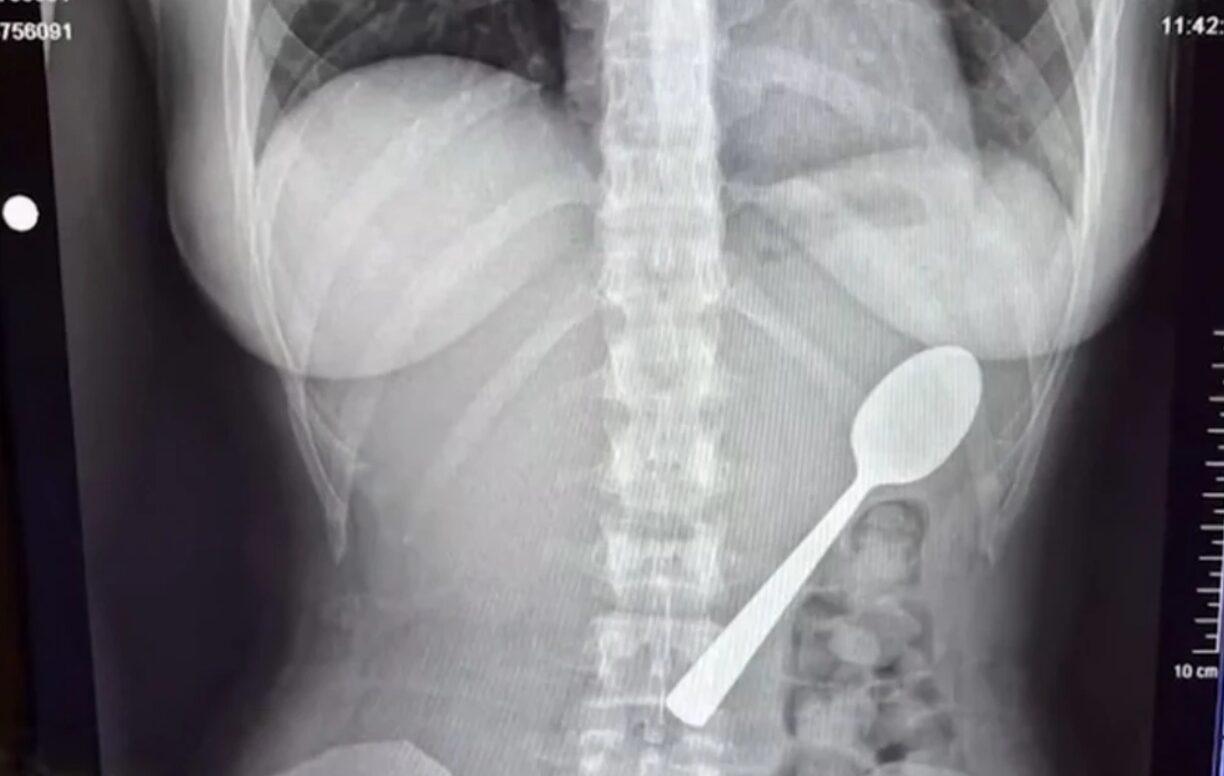

Μία 28χρονη γυναίκα κατάφερε να καταπιεί κουτάλι 17 εκατοστών και δεν είχε την παραμικρή ενόχληση. Μάλιστα αποφάσισε να επισκεφθεί τα επείγοντα ύστερα από παρότρυνση ανθρώπων από το διαδίκτυο.

Φαίνεται πως μία απίστευτη περιπέτεια έζησε μια νεαρή γυναίκα, καθώς κατάπιε ένα κουτάλι 17 εκατοστών, το οποίο κόλλησε στο στήθος της. Σύμφωνα με την ίδια δεν ένιωσε καμία ενόχληση και δεν ανησύχησε και νοσηλεύτηκε στα επείγοντα επειδή οι διαδικτυακοί της φίλοι…την συμβούλευσαν. Η ιστορία της έχει γίνει viral.

Γυναίκα κατάπιε κουτάλι 17 εκατοστών

Πιο συγκεκριμένα, η 28χρονη Reymy Amelinckx από το Βέλγιο έτρωγε γιαούρτι στον καναπέ της, όταν το σκυλάκι της, ο Μάρλεϊ, πήδηξε πάνω της. «Έβαλα το κουτάλι στο στόμα μου για να έχω τα χέρια μου ελεύθερα και να απαντήσω σε ένα μήνυμα. Ακριβώς εκείνη τη στιγμή, ο Μάρλεϊ αποφάσισε να πηδήξει πάνω μου», είπε.

«Τρόμαξα τόσο πολύ που έσκυψα το κεφάλι μου προς τα πίσω και, πριν το καταλάβω, το κουτάλι είχε κολλήσει στο λαιμό μου. Σηκώθηκα όρθια και άρχισα να πανικοβάλλομαι», είπε χαρακτηριστικά. Κι αφού δεν μπορούσε να αφαιρέσει το κουτάλι, η Reymy είπε ότι αναγκάστηκε να πάρει μια απόφαση σε κλάσματα δευτερολέπτου. Τελικά το κατάπιε και δεν είπε τίποτα στον φίλο της όταν επέστρεψε σπίτι, επειδή ντρεπόταν.

«Δεν ένιωθα καμία ενόχληση, οπότε δεν ανησύχησα», δήλωσε και σημείωσε ότι άρχισε να ρωτάει στο διαδίκτυο για την κατάστασή της. Τότε, με όσους χρήστες επικοινώνησε, την προέτρεψαν να πάει στο νοσοκομείο, τονίζοντας ότι είναι σοβαρό. Η 28χρονη παρότι δεν ένιωθε κάτι, πήγε στα επείγοντα και εκεί οι γιατροί έμειναν άναυδοι.

Αρχικά, προσπάθησαν να τραβήξουν έξω το κουτάλι, όμως ήταν αρκετά μεγάλο για να βγει φυσιολογικά, οπότε προχώρησαν σε γαστροσκόπηση. «Εκείνη η νύχτα ήταν δύσκολη, ένιωθα το κουτάλι να κινείται, μερικές φορές ακόμη και ανάμεσα στα πλευρά μου. Ήταν πραγματικά τρομακτικό. Ένιωθα φουσκωμένη και ναυτία, και δεν μπορούσα να φάω χωρίς να νιώθω περίεργα. Ο ύπνος ήταν δύσκολος, γιατί κάθε στάση μου θύμιζε το κουτάλι στο στομάχι μου», είπε η Reymy.

Εν τέλει, το κουτάλι αφαιρέθηκε σε προγραμματισμένο χειρουργείο μετά από δύο μέρες, με τη γυναίκα να προειδοποιεί τον κόσμο μετά την περιπέτειά της να ζητούν πάντα ιατρική συμβουλή, ακόμη και αν δεν αισθάνονται κάποια ενόχληση.